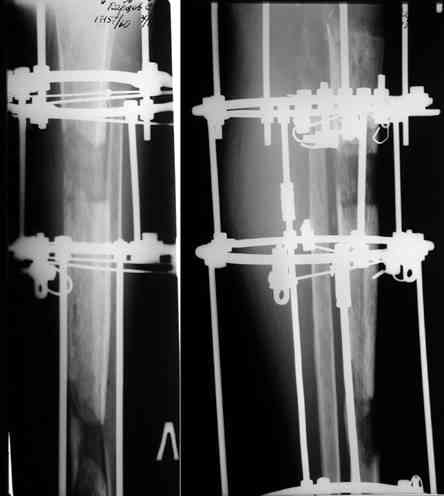

Этот стиль мне полностью приемлем и понятен. Наверно я бы поступил также. Но статистика упрямая вещь. Сколько у тебя или у другого врача опыта по замещению дефектов бедра? У меня за 25 лет работы 3, и еще около 15 случаев удлинения бедра. Случай у тебя очень сложный. Если Вы выбираете Илизаровскую методику то надо на в/з хорошую дугу, не менее 4-5 спиц с напайками.Стержни хороши когда кость не измучена и на 2-4 месяца. Здесь аппарат на 6-8 месяцев. Если есть желание я только за, и

желаю только успеха и чтоб все трудности которые будут преодолел.

Прикрепляю пример замещения дефекта бедра 20 см, после резекции по поводу опухоли, эндопротеза Сиваша, вялотекущего остеомиелита со свищами в течении 3 лет. Получилось хорошо и всего за 6 месяцев в аппарате. Колена не было. У Вас случай сложнее. Это было в 1998г. Я работал в ЦИТО и у меня было 4 больных, я занимался им с утра до ночи. Сейчас 60 больных и операций в нашем отделении 25-30 в неделю.Если могу чем помочь - нет проблем.